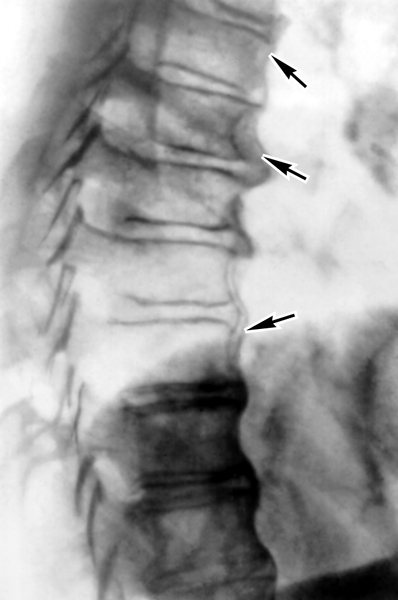

Диагностика

Процесс постановки диагноза начинается с визита к врачу. Сначала проводится опрос пациента, в ходе которого выясняются симптомы и возможные причины недуга. Уточняется образ жизни пациента, его режим питания, труда и отдыха. Затем следует физикальный осмотр, во время которого специалист оценивает степень поражения позвоночника с помощью визуального осмотра и пальпации.

Далее назначаются различные обследования:

- анализы крови, мочи и кала;

- панорамная рентгенография;

- магнитно-резонансная и/или компьютерная томография.

Для формирования полной клинической картины могут быть рекомендованы консультации у узкоспециализированных врачей. Это помогает выявить и устранить заболевания, ослабляющие организм. После завершения комплексного обследования и установления точного диагноза врач разрабатывает план лечения спондилеза.